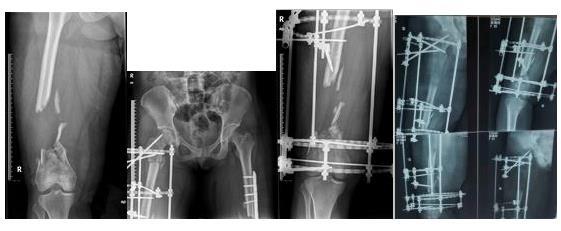

林某 车祸伤致:右侧股骨下段开放性粉碎骨折并10cm骨缺损,左下肢股骨下段粉碎性骨折

左下肢